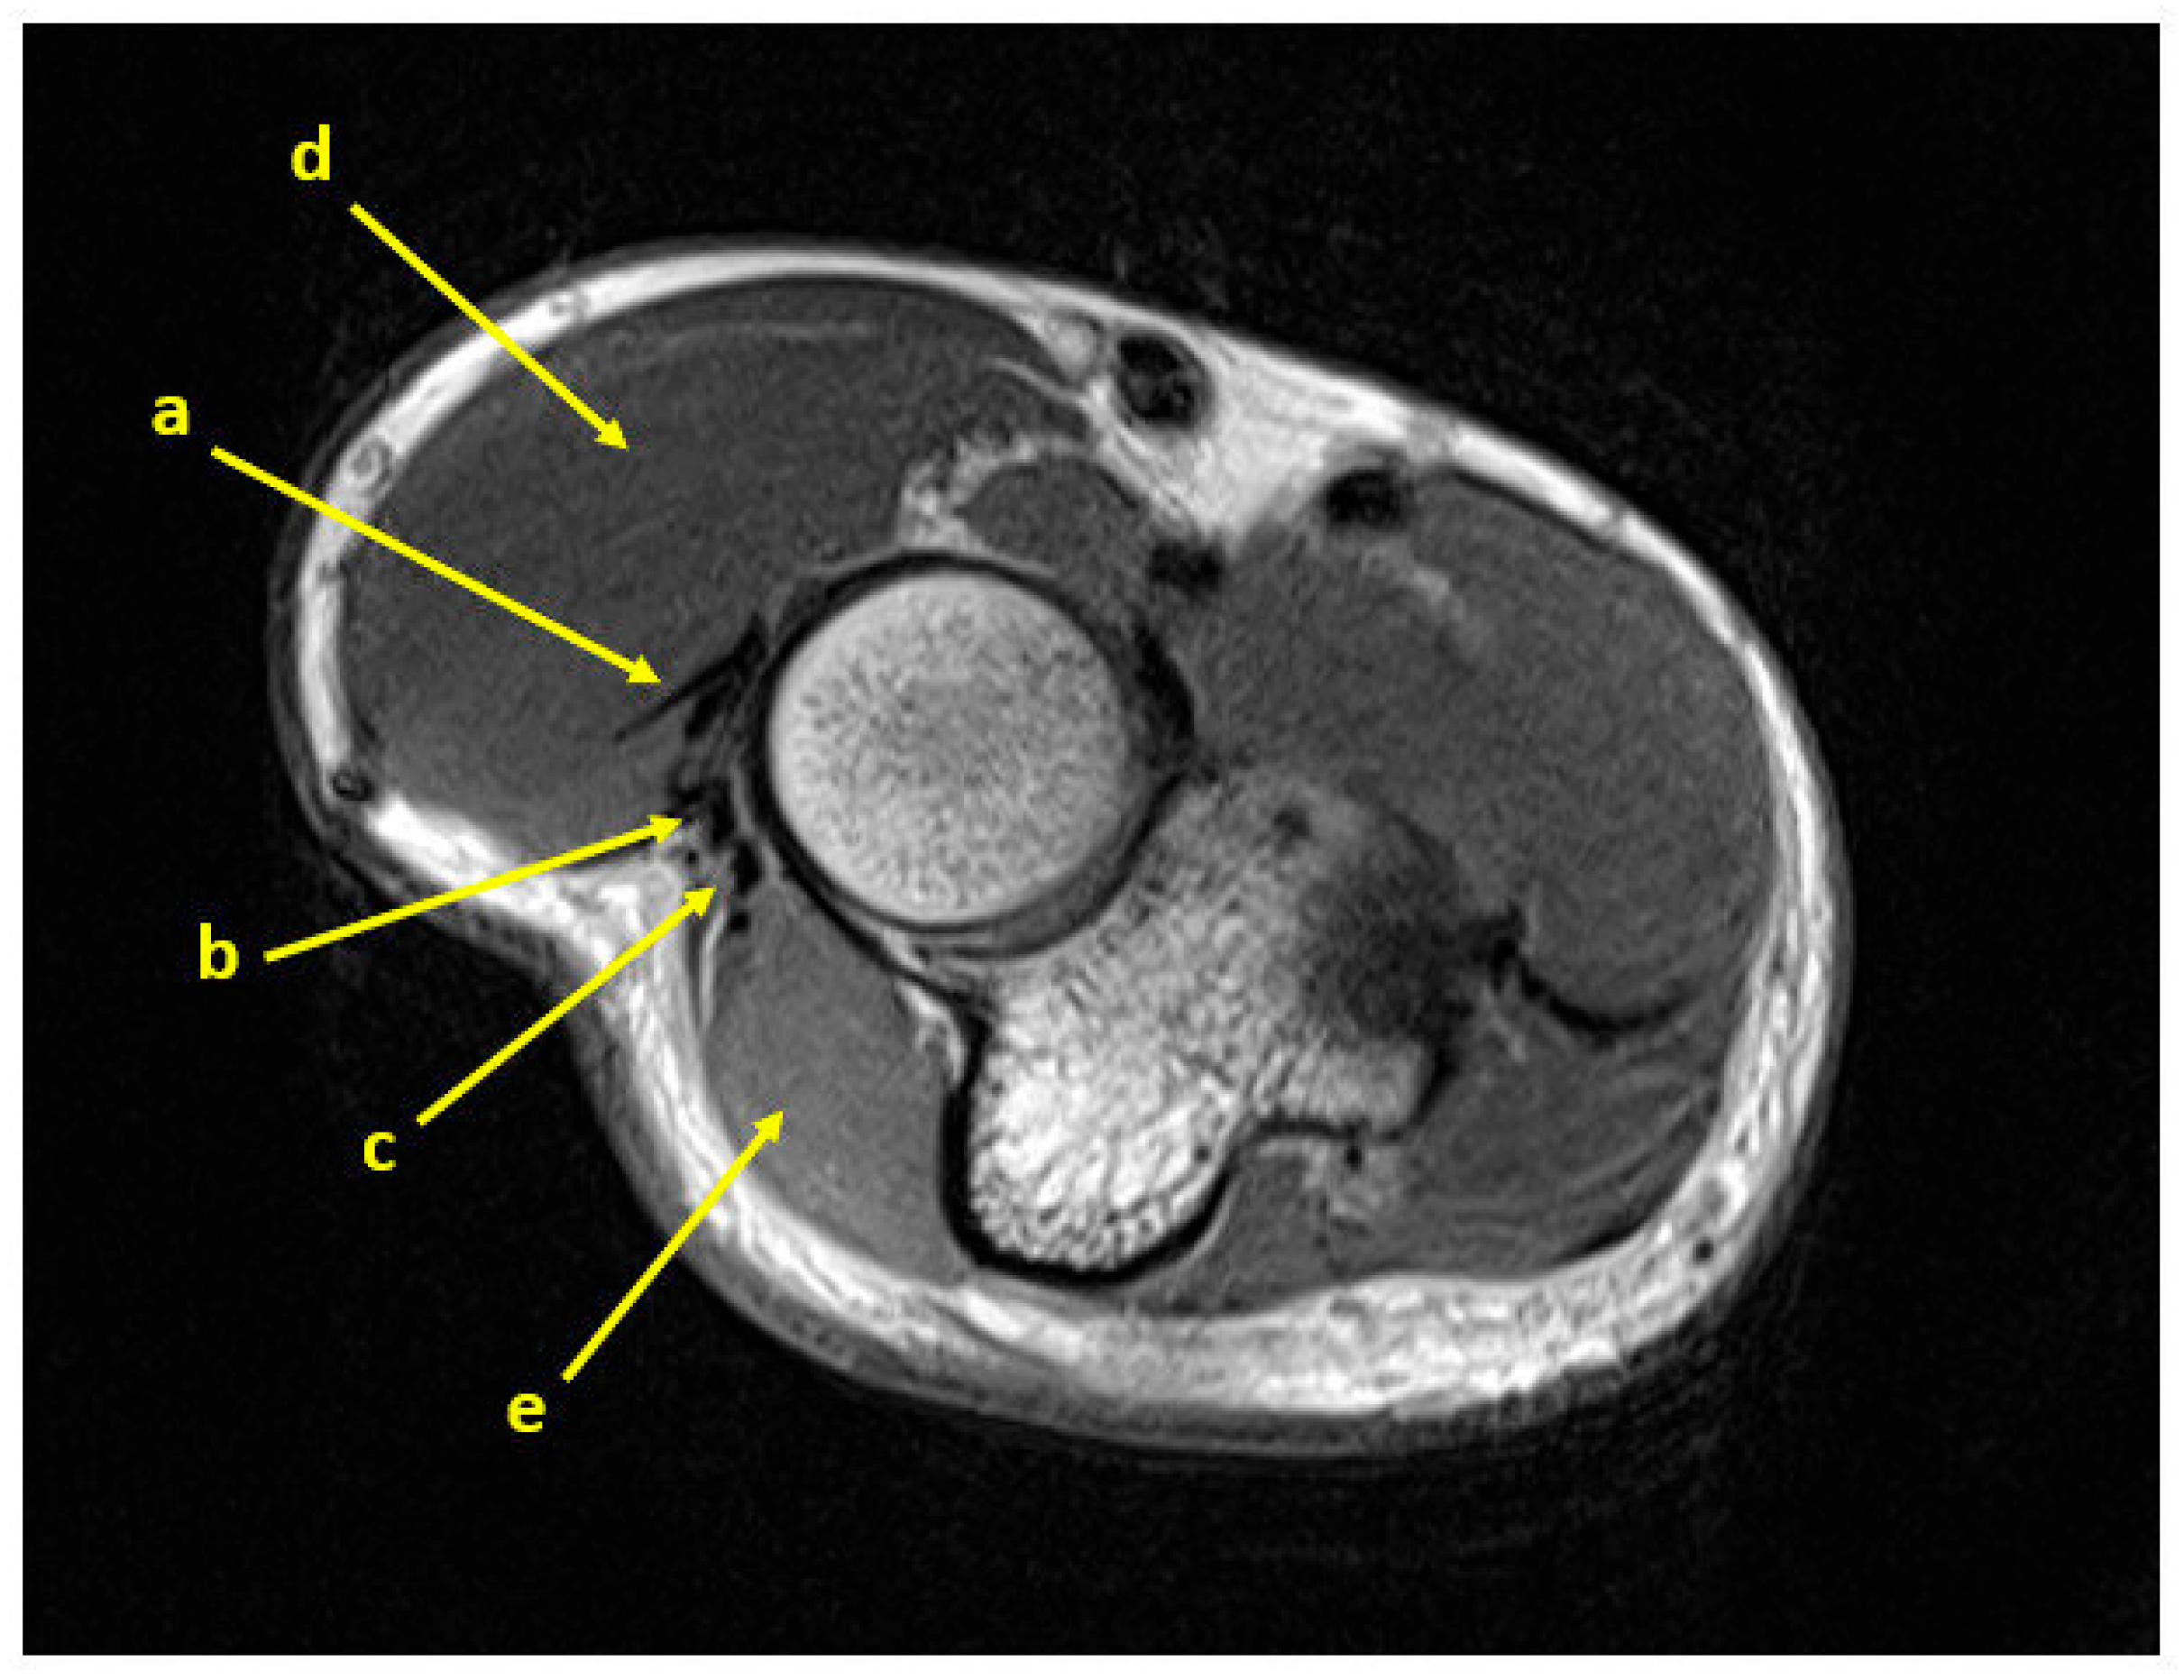

2.2. Surgical Technique